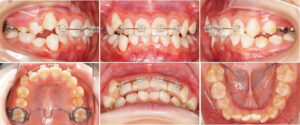

6才女子の症例です。

歯並びがガタガタしているのが気になる、食事の時に食べ物が歯に挟まりやすい、と相談に来られました。

詳しく検査したところ、顎の位置が不安定だったため、まず「顎の位置を安定させる装置(スプリント)」を使って顎位の安定を図りました。

その後、矯正治療を行いました。

一期治療では、まだ顎の骨が成長途中なので「ヘッドギア」と呼ばれる特別な装置で、顎の成長をコントロールし、乳歯から永久歯への生え変わりがスムーズになるようサポートしました。

二期治療では、叢生(デコボコ)上顎前突(出っ歯)の改善のために小臼歯を抜歯して、歯を並べるスペースを作りました。

そして、さらにきれいに歯並びを整えるため、マルチブラケット装置(ワイヤーの装置)や上顎に力をかける器具(パラタルバー)を使いました。

治療後は、歯並びがきれいになって自信を持って笑えるようになりました。食事の時も、食べ物が挟まりにくくなり、ご家族にもとても喜んでいただきました。

矯正治療費用:一期治療 ¥420,000 二期治療 ¥430,000

矯正治療期間:一期治療 1年5ヶ月 二期治療 3年8ヶ月

矯正治療回数:一期治療 8回 二期治療 20回

治療前

一期治療中

二期治療中

治療後